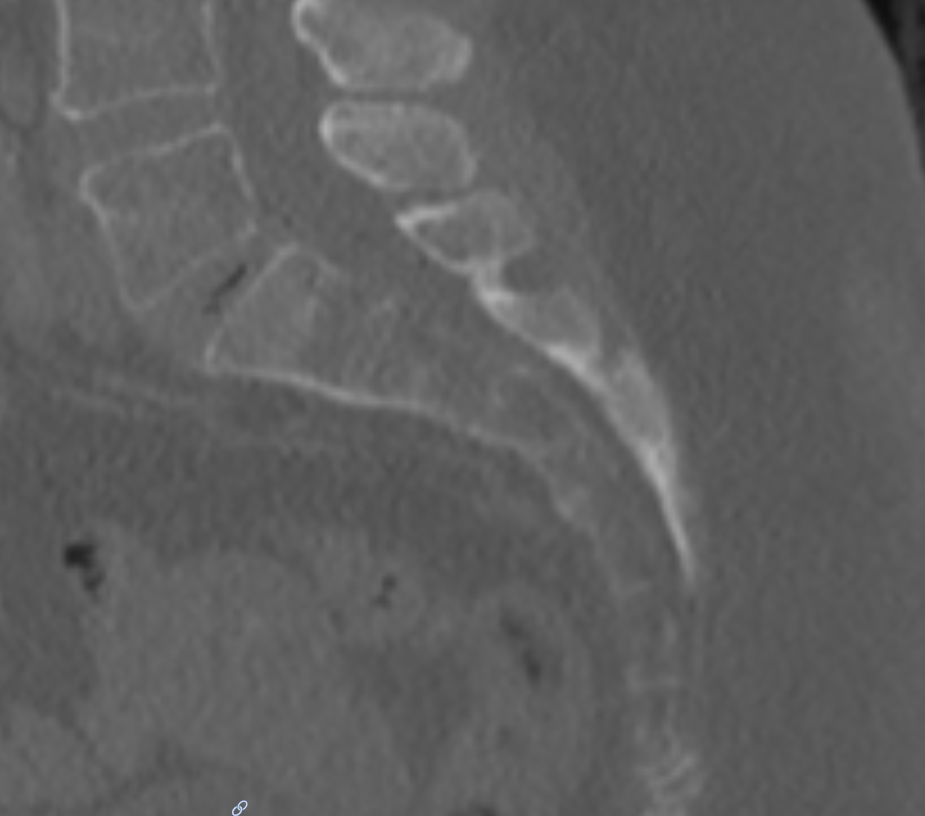

Sagittales CT Bild des Os sacrum

Sagittales CT Bild des Os sacrum.